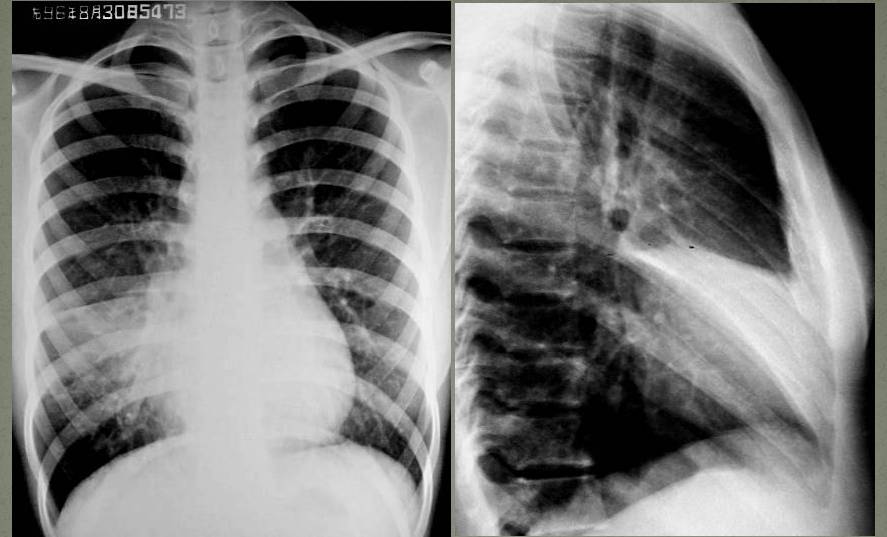

肺叶不张和肺段不张各有何X线表现?(1)右肺上叶不张:横裂上移呈折扇形或三角形致密阴影,尖端指向肺门,甚至全部位于上纵隔旁。(2)右肺中叶不张:右心缘旁致密阴影,上缘不超过肺门。直立的正位片上常显影不清。侧位片显示较为清楚,呈三角形、梭形或线形,尖端指向肺门。

↓ 右侧气胸(肺压缩约70%),右肺上叶肺段不张(尖端指向肺门)